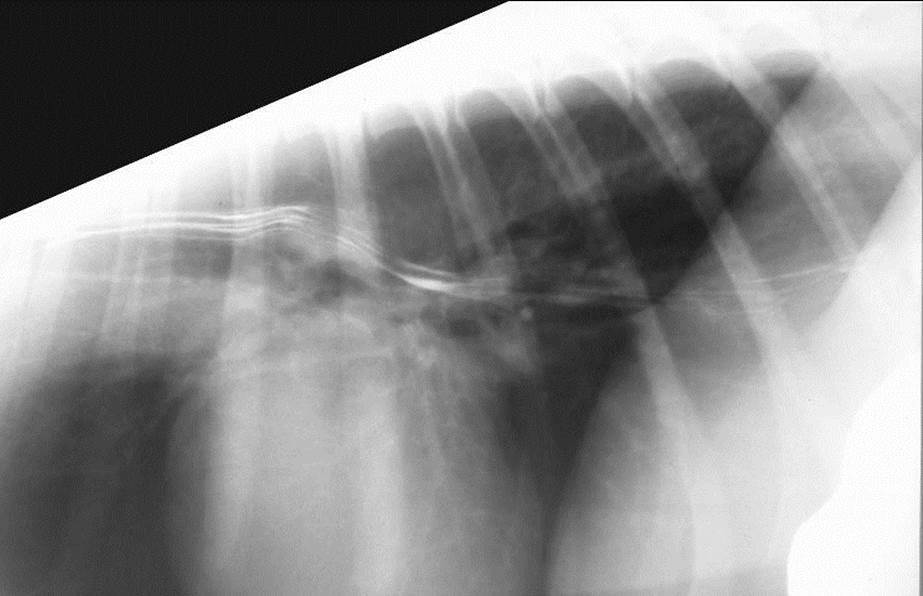

Look at this barium swallow pattern in a cat?

Change in muscle type in cat leads to this Heringbone pattern